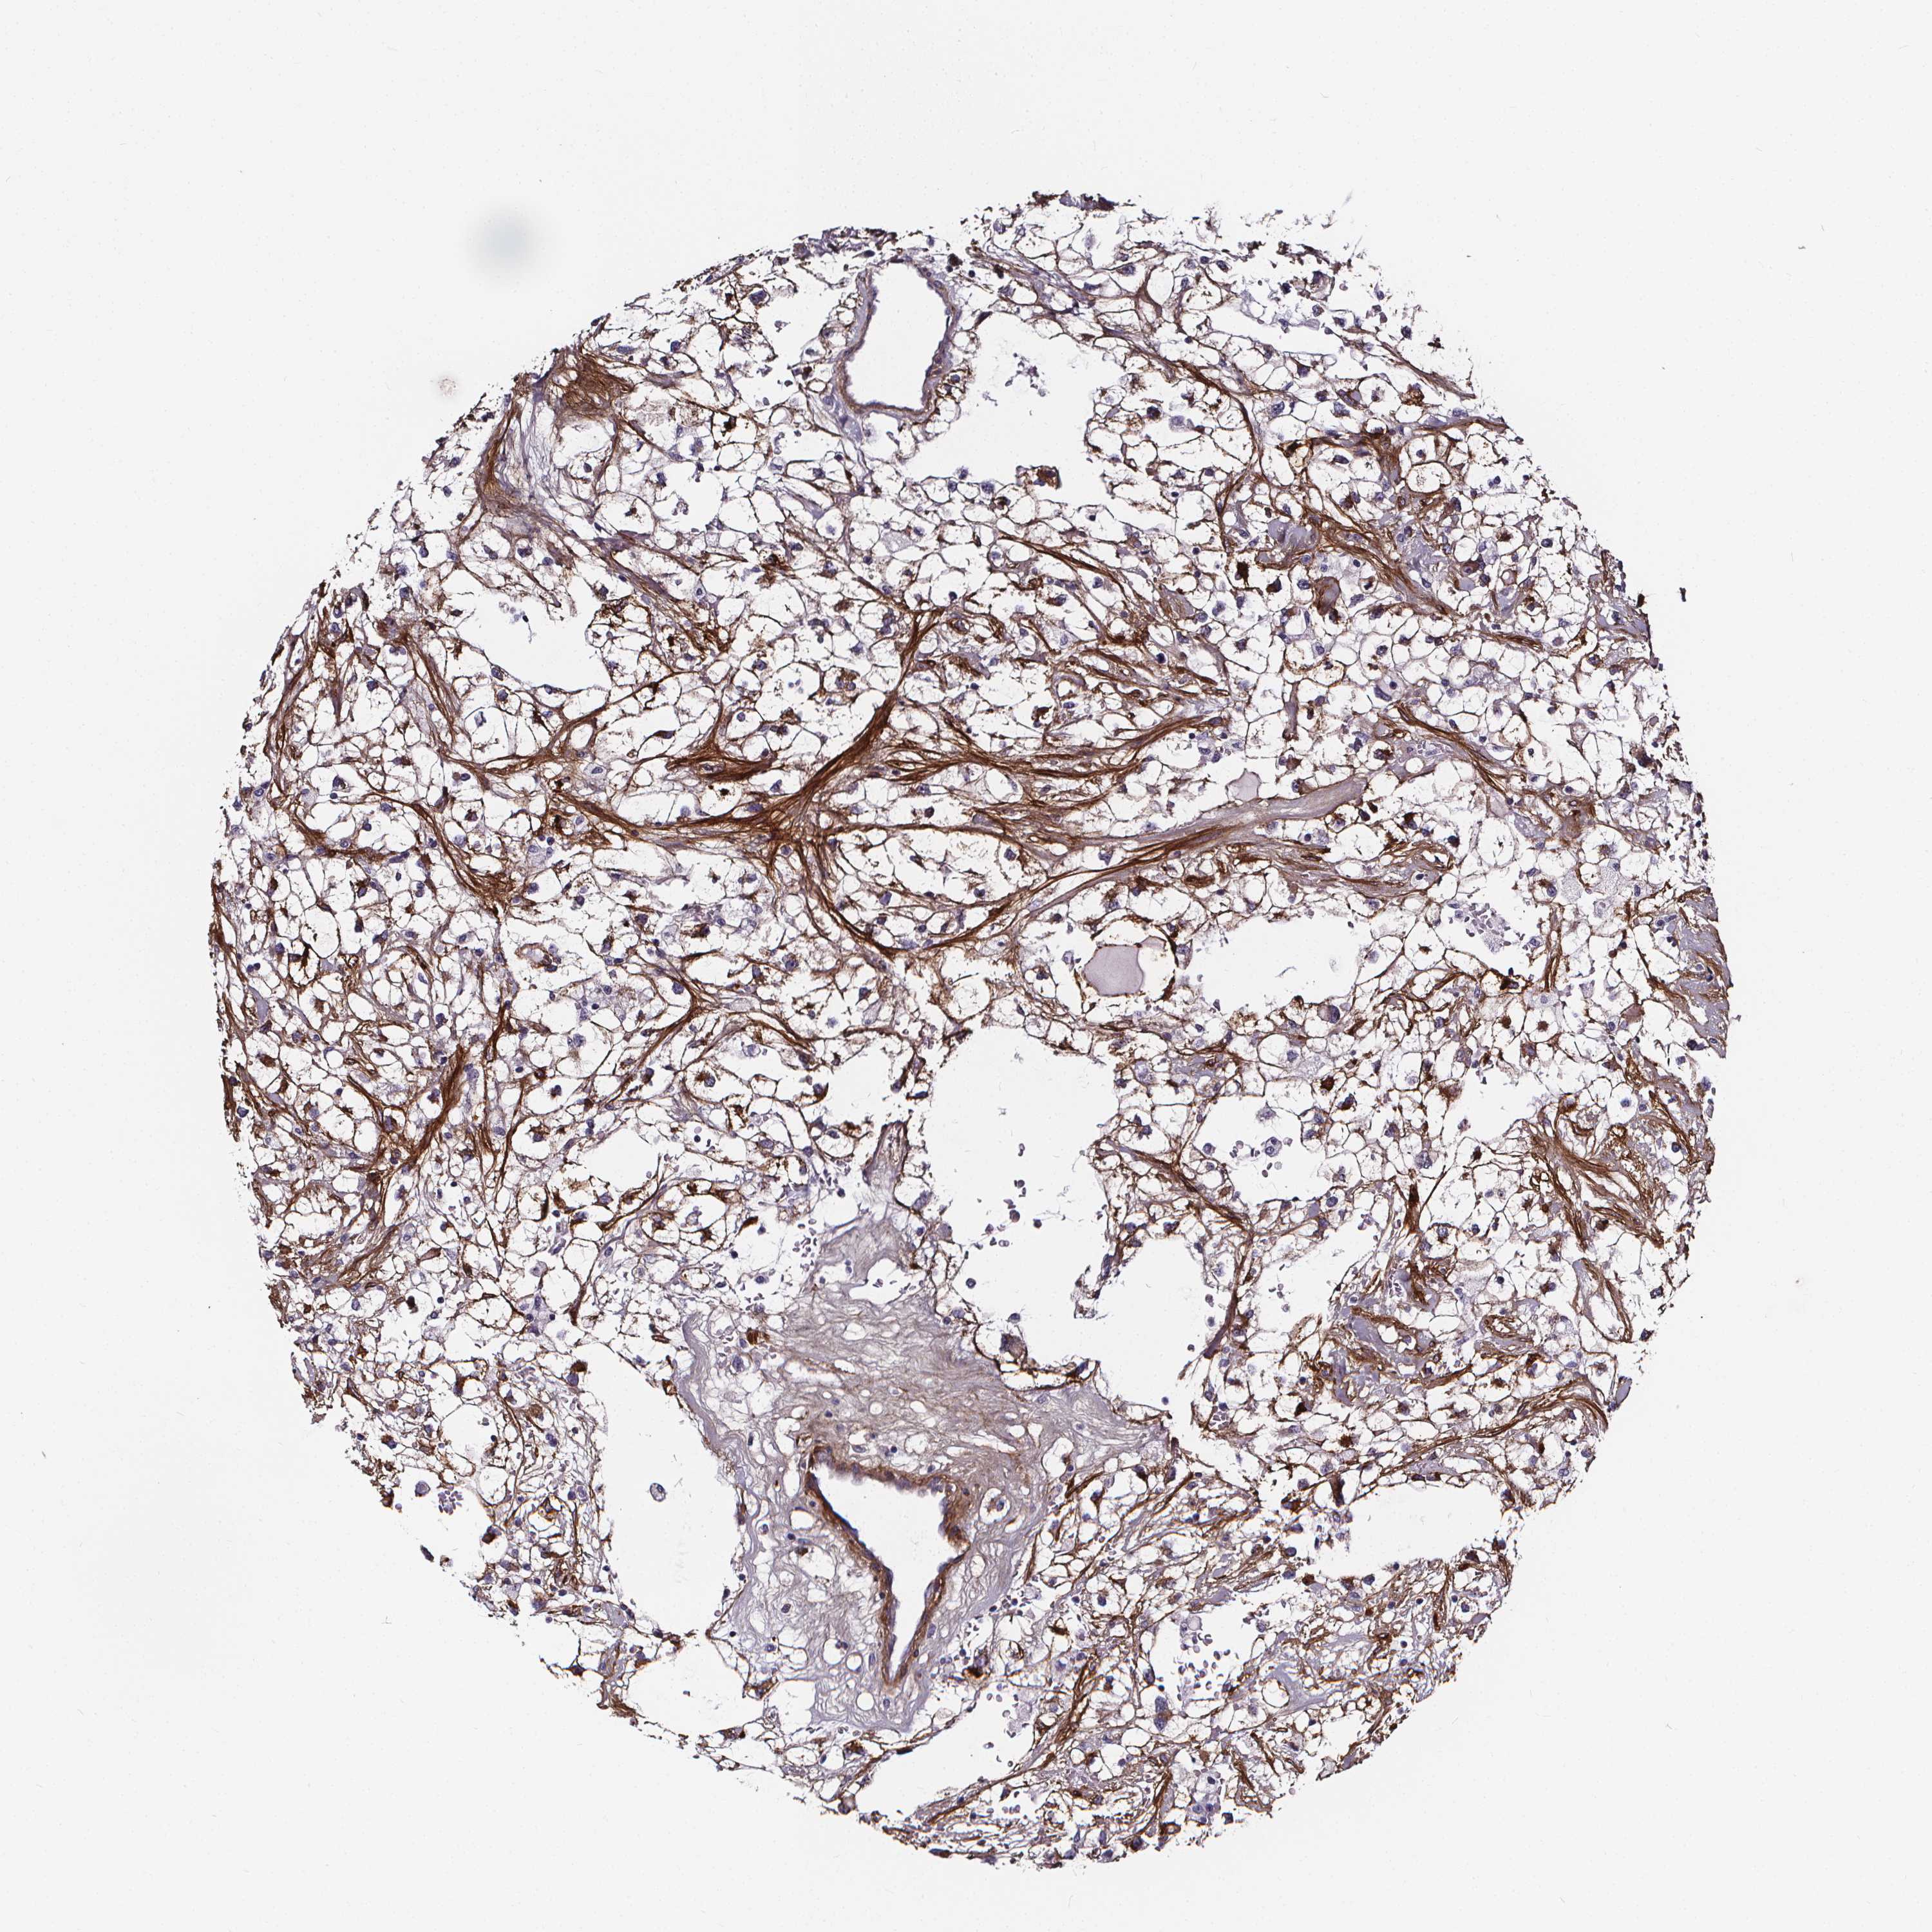

KIDNEY RENAL PAPILLARY CELL CARCINOMA (TCGA) - Interactive survival scatter ploti

The Survival Scatter plot shows the clinical status (i.e. dead or alive) for all individuals in the patient cohort, based on the same data that underlies the corresponding Kaplan-Meier plots. Patients that are alive at last time for follow-up are shown in blue and patients who have died during the study are shown in red.

The x-axis shows the expression levels (FPKM) of the investigated gene in the tumor tissue at the time of diagnosis. The y-axis shows the follow-up time after diagnosis (years). Both axes are complimented with kernel density curves demonstrating the data density over the axes. The top density plot shows the expression levels (FPKM) distribution among dead (red) and alive patients (blue). The right density plot shows the data density of the survived years of dead patients with high and low expression levels respectively, stratified using the cutoff indicated by the vertical dashed line through the Survival Scatter plot. This cutoff is automatically defined based on the FPKM cutoff that minimizes the p-score. The cutoff can be changed by dragging the vertical line or by entering a cutoff value in the square labeled "Current cut-off".

Under the Survival Scatter plot the p-score landscape (black curve; left axis) is shown together with dead median separation (red curve; right axis). Dead median separation is the difference in median mRNA expression between patients who have died with high and low expression, respectively. It is calculated as follows: median FPKM expression of dead patients with high expression - median FPKM expression of dead patients with low expression. This is intended to aid the user in visually exploring custom cutoffs and the associated p-scores and dead median separation.

Individual patient data is displayed and can be filtered by clicking on one or more of the category buttons on the top of the page. Categories describing expression level and patient information include: high, low, alive, dead, female, male and tumor stages. The scale of the x-axis can be toggled between linear and log-scale by clicking on the "x log" button. Mouse-over function shows TCGA ID, patient information and mRNA expression (FPKM) for each patient.

& Survival analysisi

Kaplan-Meier plots summarize results from analysis of correlation between mRNA expression level and patient survival. Patients were divided based on level of expression into one of the two groups "low" (under cut off) or "high" (over cut off). X-axis shows time for survival (years) and y-axis shows the probability of survival, where 1.0 corresponds to 100 percent.

AEBP1 is potential prognostic, high expression is unfavorable in Kidney Renal Papillary Cell Carcinoma (TCGA)